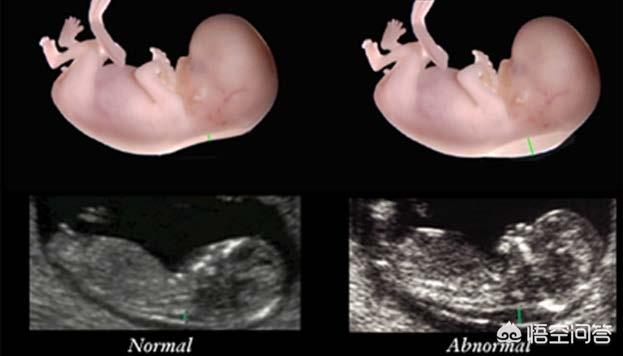

2、颈后透明带的厚度和是否有疾病有关系

正常胎儿存在这一透明区代表胎儿生理性新陈代谢所产生的液体积存,是对胎脑一过性的过度灌注的保护性表现 。

如果透明带增厚,则暗示胎儿染色体异常、胎儿结构畸形、少见的基因综合征以及自然流产等。如21-三体、18-三体、13-三体异常,先天性心脏病、非免疫 性水肿、颈部囊状淋巴管瘤早期等。